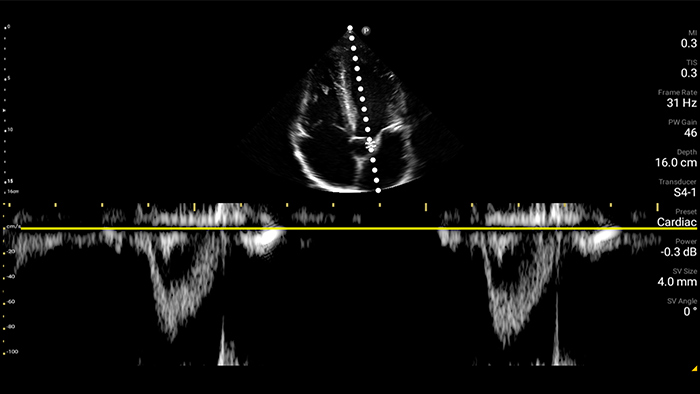

Every second counts in cardiac care

Heart attack patients need immediate care. Lumify's cardiac presets can help patients get diagnosed faster to improve their outcomes.

• 4 to 1 MHz extended operating frequency range • 2D, color Doppler, M-mode, advanced XRES and multivariate harmonic imaging • High-resolution imaging for abdominal and cardiac applications: Cardiac, OB/GYN, Lung, Abdomen and FAST imaging preset optimizations Lumify aids life-saving technology in prehospital setting